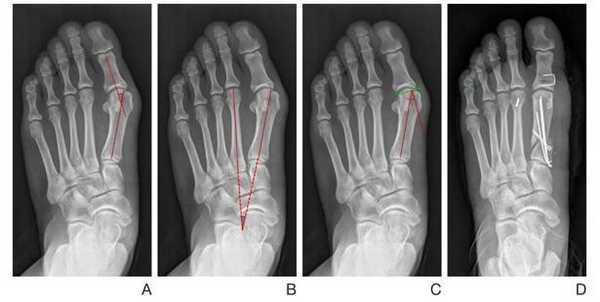

SCARF

Z-образная остеотомия Scarf – это золотой стандарт лечения вальгусной деформации. Она позволяет установить головку плюсневой кости под нужным углом. В ходе хирургического вмешательства врачи также убирают деформацию суставной капсулы и меняют направление некоторых сухожилий.

Когда операции Scarf недостаточно – хирурги делают проксимальную клиновидную остеотомию или артродез.

Важно! У большинства пациентов с вальгусной деформацией врачи выявляют костную мозоль (экзостоз). Нарост локализуется на медиальной поверхности головки I плюсневой кости. Как правило, его удаляют во время всех операций, в том числе и малоинвазивных.

Не путайте спиливание костного нароста с остеотомией. Это две совершенно разные манипуляции. Цель первой – убрать косметический дефект, второй – восстановить нормальное функциональное состояние стопы. Помните, что удаление костной мозоли (операция Шеде) не в состоянии излечить вас от Hallux Valgus.

Артродез при вальгусной деформации

Артродезирование – это полное обездвиживание плюсне-клиновидного сустава путем соединения формирующих его костей. Операцию делают лицам с поперечно-распластанной деформацией и Hallux Valgus с гипермобильностью I плюсне-клиновидного сустава.